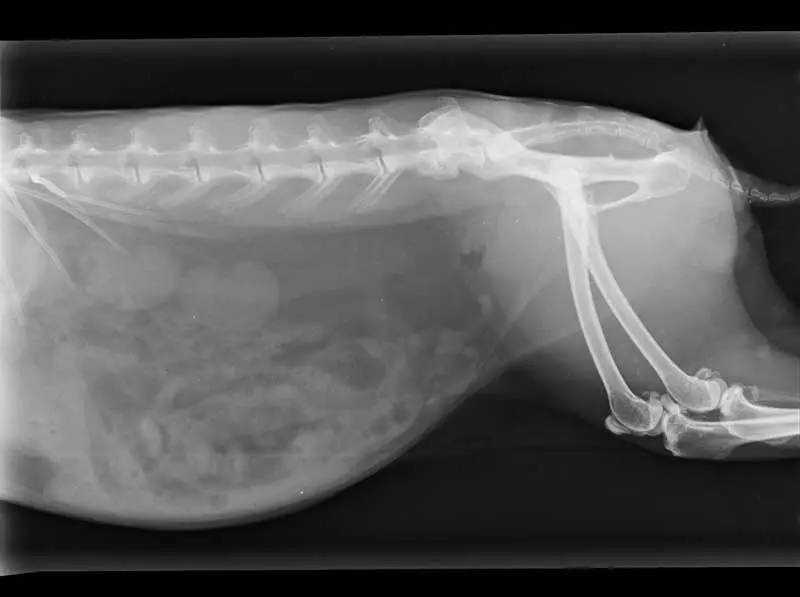

Figure 5 shows a rabbit with bridging spondylosis of the last two lumbar vertebrae.

Anecdotally, the authors have seen several cases where this pattern has been seen, and then, after a fall or a particularly over-enthusiastic run or jump, potentially after being chased or scared by a predator, the rabbit has been acutely much worse. The suspicion here is that the bridge of callus between those previously fused vertebrae has fractured or become unstable, leading to an acute on chronic source of additional, severe pain.